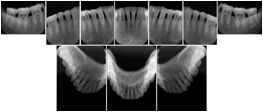

Intra-oral radiography typically involves acquisition of multiple images of various parts of the dentition. Many digital radiographic systems offer customized templates that are used for displaying the images in a study on the screen. These templates may also be referred to as mounts or view sets. The Structured Display Object represents a standard method of encoding and exchanging the layout and intended display of Structured Displays. A structured display object created in this manner could be stored with a study and exchanged with images to allow for complete reproduction of the original exam.

3. A dental provider wishes to capture a series of DICOM IO images for the patient’s dentition. The tooth morphology, teeth are divided into molars, premolars, canines and incisors, and a number of images for each jaw. The anatomic information was captured utilizing the triplet of schema. This standard code sequence is based on ISO 3950-2010, Dentistry - Designation system for teeth and areas of the oral cavity.

In most standard cases, images are oriented in structured layouts. These structured displays are useful to be shared between providers for reference purposes.

Table OO.1.1-1 shows structured display standard templates, where Viewset ID is based on the Japanese Society for Oral and Maxillofacial Radiology (JSOMR) classification provided by JIRA (Japan Medical Imaging and Radiological Systems Industries Association, www.jira-net.or.jp). Expected or typical teeth to be imaged location, region and designation codes are based on ISO 3950-2010, Dentistry - Designation system for teeth and areas of the oral cavity. For all the hanging protocols listed in OO.1.1-1, the value to use for Hanging Protocol Creator (0072,0008) is "JSOMR" and the value to use for Hanging Protocol Name (0072,0002) does not include "JSOMR" (e.g., "DL-S001A", not "JSOMR DL-S001A").